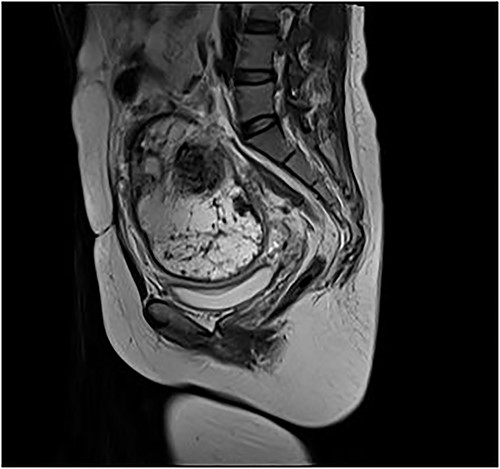

A 35-year-old female was diagnosed with prolonged menstruation for more than 10 years and a 2-day history of lower abdominal distension and distention to our gynaecology department. She is a reproductive woman, with two previous cesarean sections, 11 and 4 years ago, respectively, and one laparoscopic myomectomy 9 years ago. Furthermore, there were no reports of abnormalities after the operations in the follow-up. On examination, she appeared mildly anxious and pessimistic due to the large mass but with normal vital signs. A mass of about 12 × 9 cm2 with moderate texture and mobility was obtained in the right side of the pelvis by palpation. Her hemoglobin was 117 g/L, red blood cell count was 3.88 × 109 g/L, white blood cell count was 16.17 × 109/L, platelet count was 256 × 109/L and the percentage of neutrophils was 87.5%.Additionally, her CA-125 was 56.04 U/ml and HE-4 was 53.70 pmol/L. Gynecologic transvaginal ultrasound revealed the following: (i) weakly echogenic nodules in the parenchyma of the uterus: myoma? (ii) No echo at the lower incision of the anterior uterine wall: diverticulum? (3) Mixed echogenic mass in the pelvis: teratoma? (iv) Mixed occupancy in the left adnexal area: tubal effusion? Pelvic enhancement MRI revealed the following (Fig. 1) (i) Right pelvic adnexal area showing mass-like abnormal signal: chocolate cyst? Encapsulated cystic lesion? Teratoma? (ii) Possible cyst in the left adnexal region; the isthmus of the anterior wall of the uterus is symptomatic. (iii) Multiple irregular nodular abnormal signals in the anterior and posterior margins of the lower uterine segment: myxoma with degeneration? Other? (iv) Multiple small lymph nodes in the pelvic wall bilaterally; small amount of pelvic fluid; soft tissue swelling around the pelvic wall. Considering that the large mass in the pelvic and more than 10 years of prolonged periods of the patient, she underwent the hysteroscopic and laparotomy exploration after the control of infection.